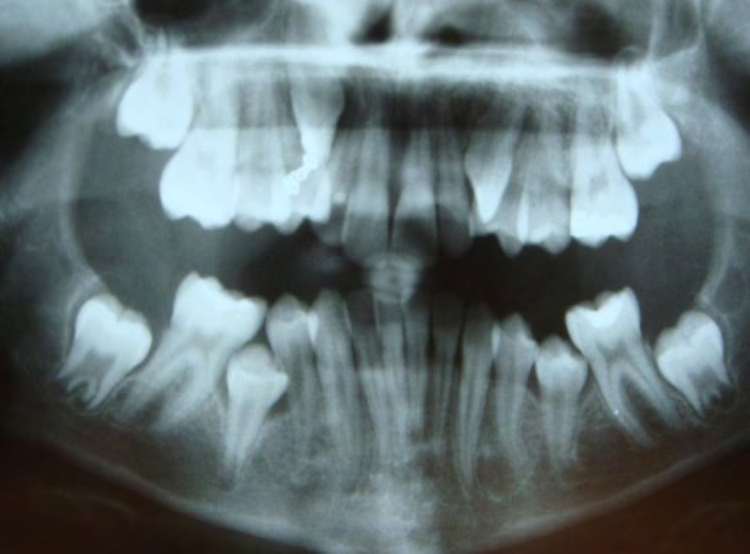

All of the patients below had been told they required extractions by orthodontists, some insisting that they could not be treated without extractions.

They were all treated without extractions, head gear or facemasks at Vakresmil and represent just a small sample of cases treated between 2004–2014.

The patient below had severe crowding of both upper canines and the lower right 5. The upper 4’s and 2’s were actually in contact.